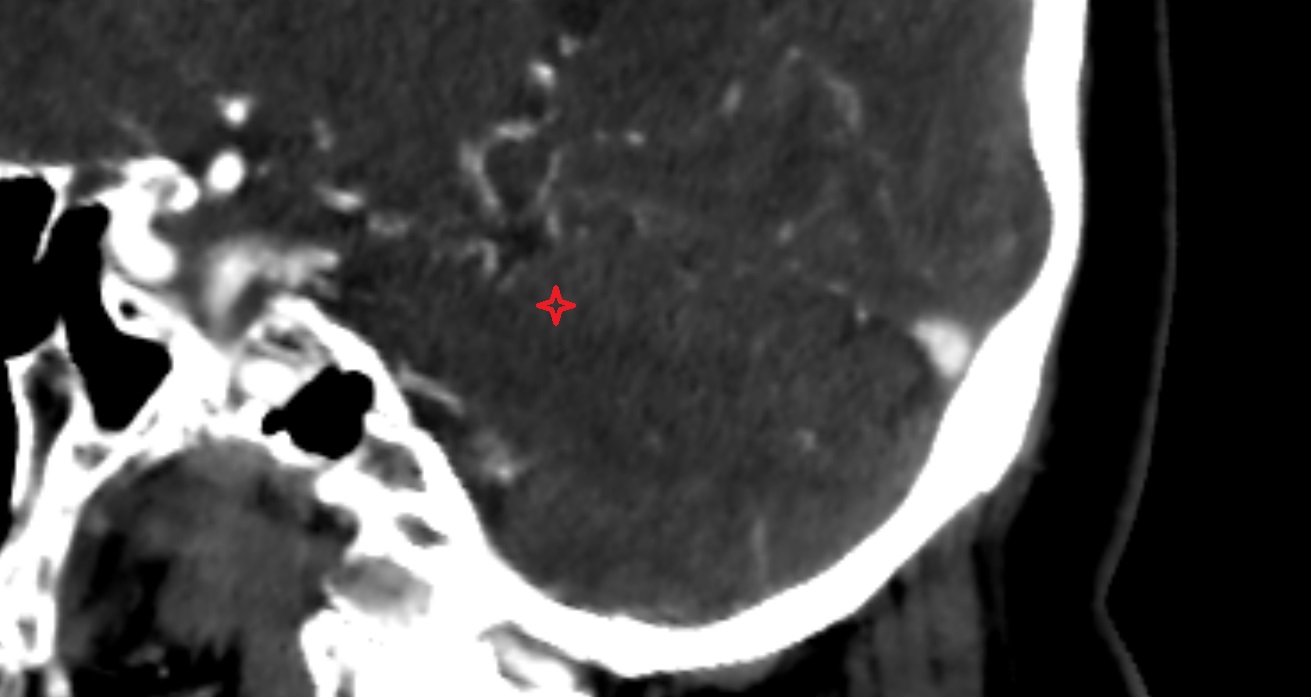

- Cerebellum